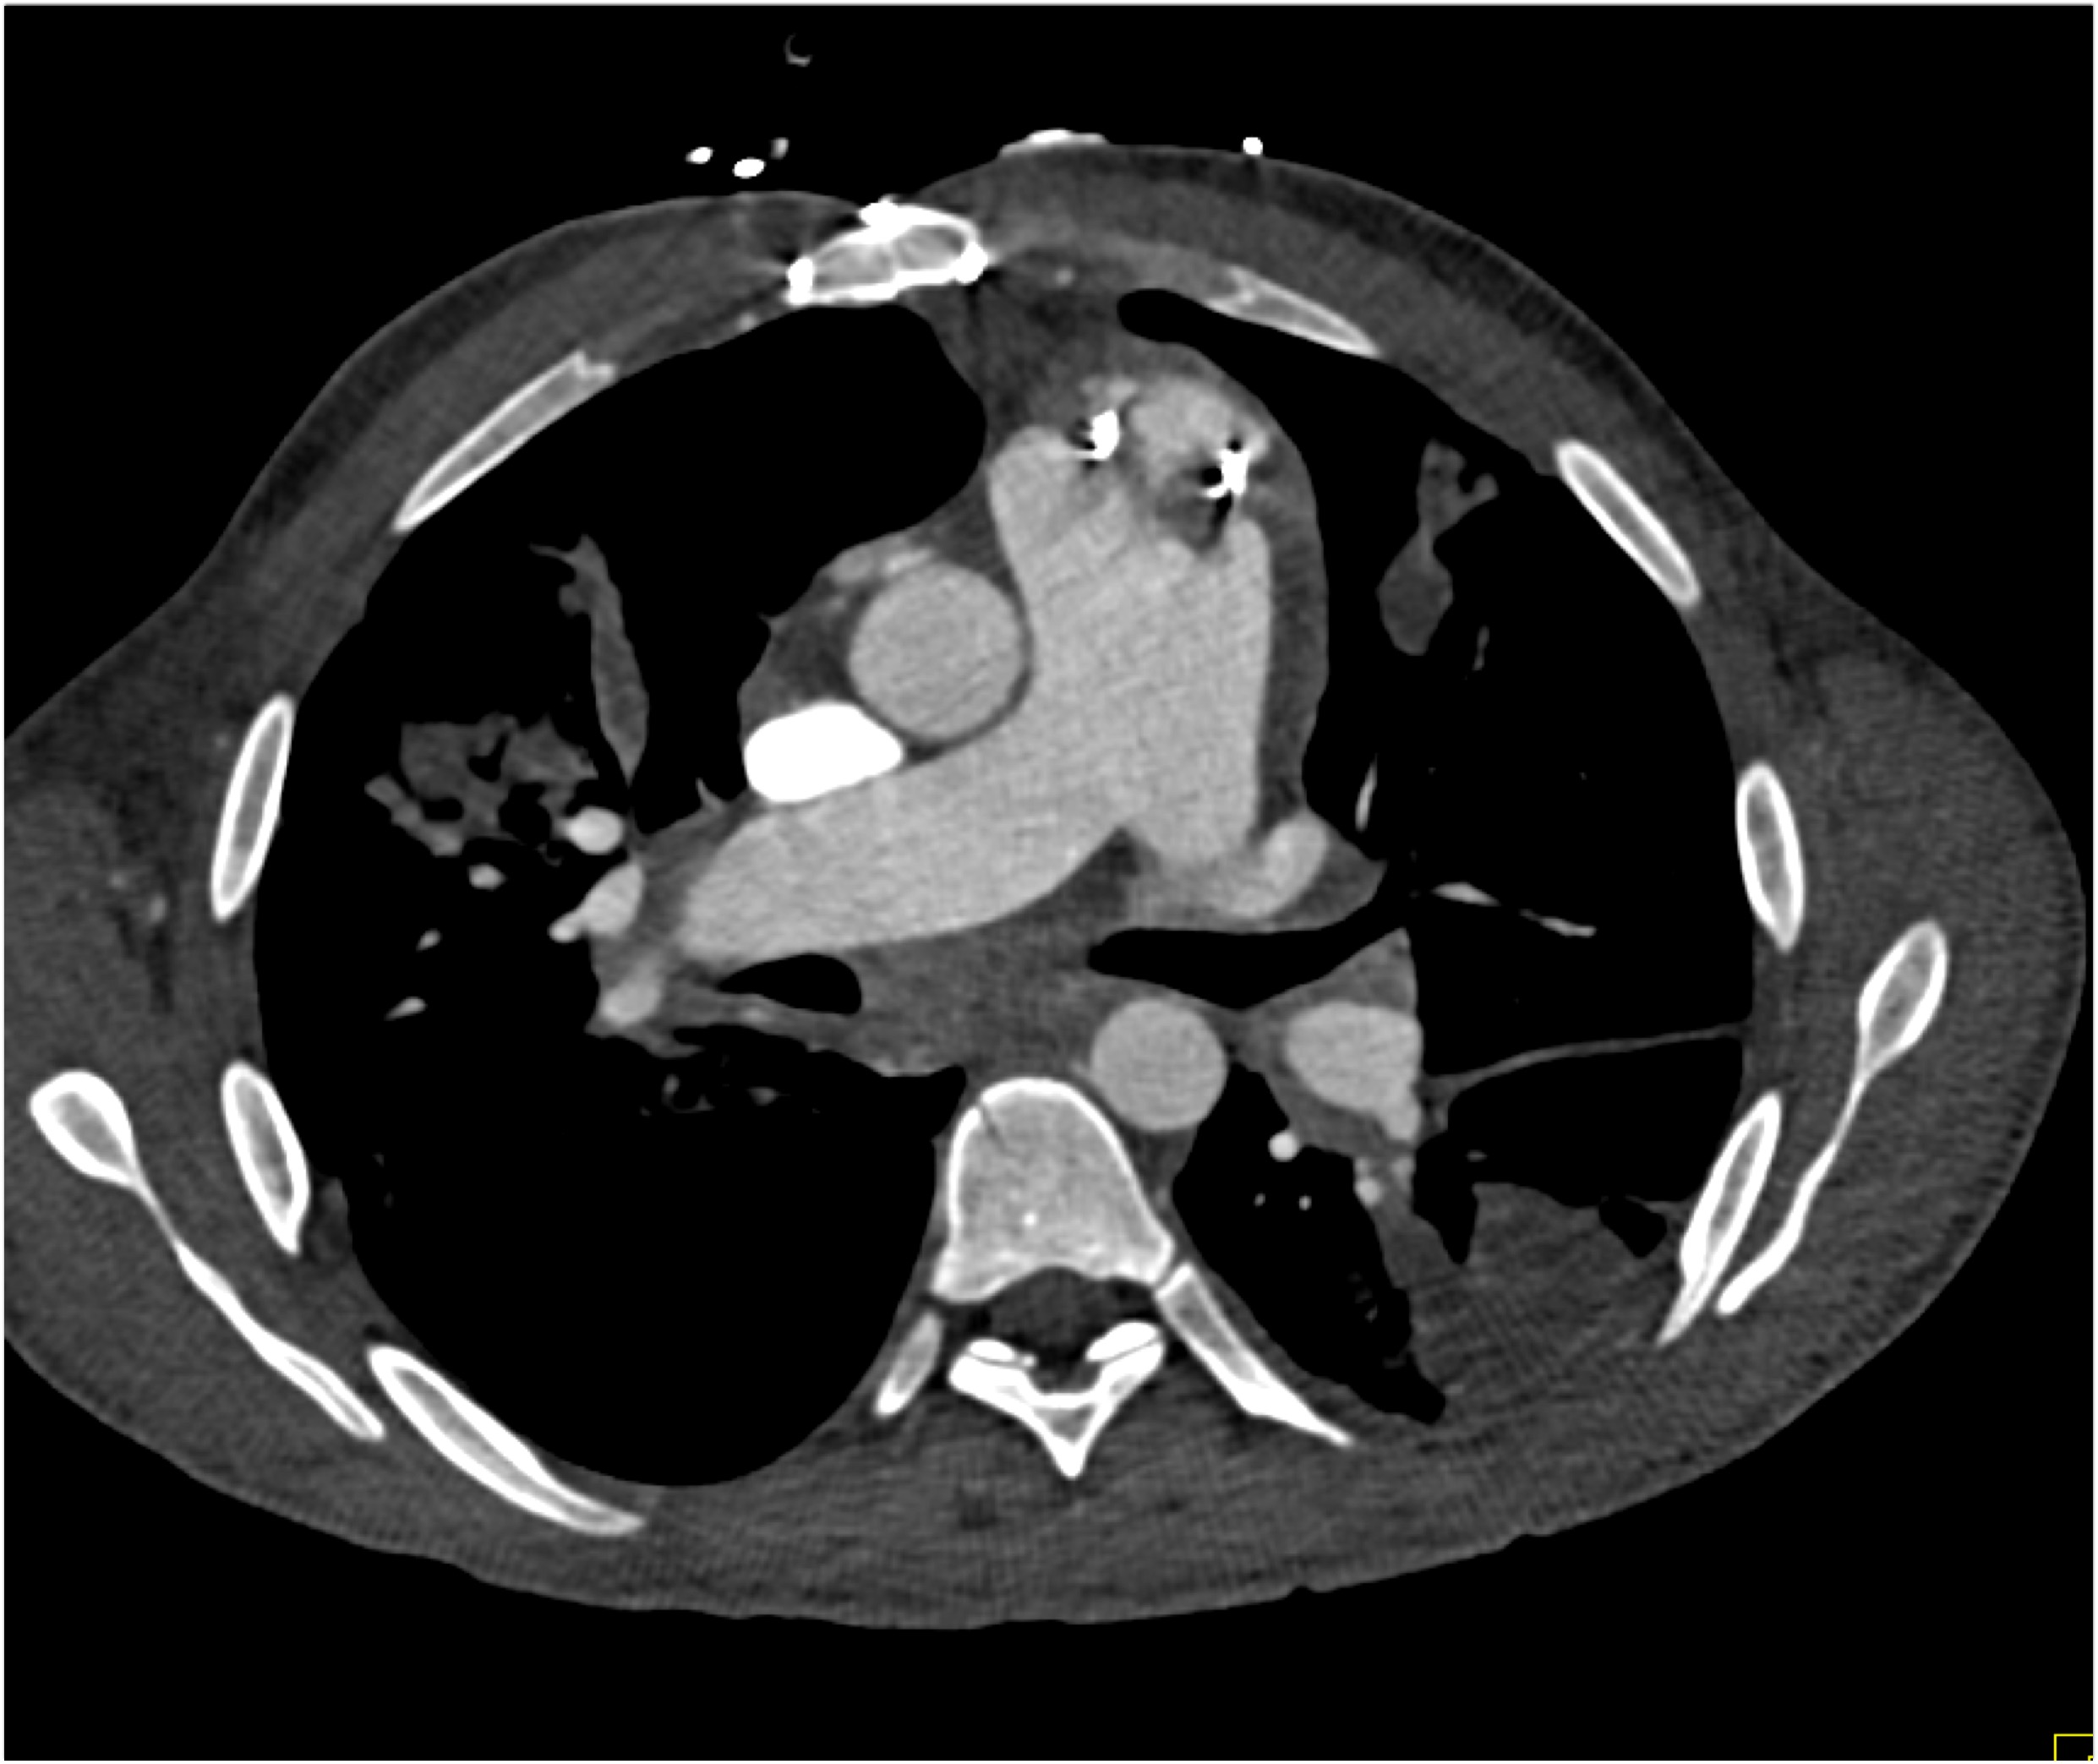

The most likely diagnosis in this case is?

vegetations in pulmonary valve

failed pulmonic valve

normal appearance of repaired pulmonary valve

abscess of the pulmonary artery